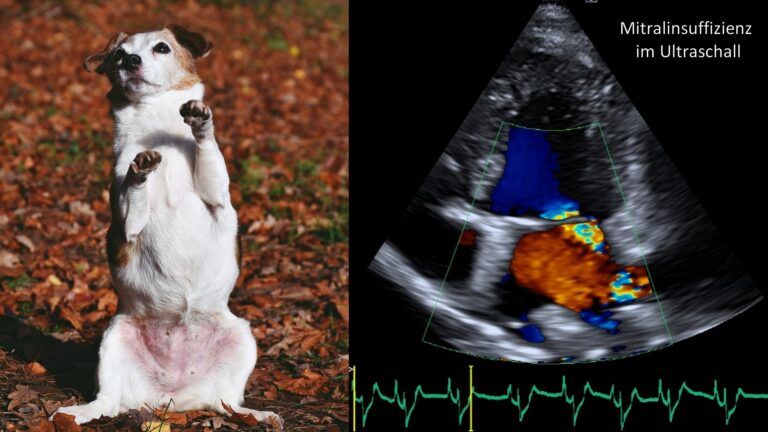

Die häufigsten erworbenen Herzerkrankungen sind Herzmuskelerkrankungen (v.a. bei der Katze) und Herzklappenerkrankungen (v.a. beim Hund). Es kann ein verdickter Herzmuskel vorliegen (Hypertrophe Kardiomyopathie, HCM der Katze) oder eine Schwäche und Ausdünnung des Herzmuskels (Dilatative Kardiomyopathie, DCM, vor allem bei großen Hunderassen). Die degenerative Herzklappenerkrankung führt zur Klappenundichtigkeit (= Insuffizienz). Der häufigste Befund in der Praxis ist die Mitralklappeninsuffizienz.

Um eine Herzerkrankung korrekt zu diagnostizieren reicht es nicht, ein Tier abzuhören. Das Vorliegen eines Herzgeräuschs oder einer Rhythmus-Veränderung ist nicht beweisend für eine Herzerkrankung. Beim Verdacht auf eine Herzerkrankung müssen mindestens ein Herzultraschall und ein EKG durchgeführt werden. Beides ist am wachen Patienten möglich und für das Tier nicht belastend. Nur mithilfe dieser Untersuchungsmethoden kann eine klare Diagnose gestellt werden. Diese ist nötig, um eine zu planen. Es gibt weitreichende Therapieoptionen, die von Medikamenten über Fütterungs- und Management-Maßnahmen bis hin zu Operationen reichen. Wichtig ist außerdem, Begleiterkrankungen oder andere Grundursachen zu finden.